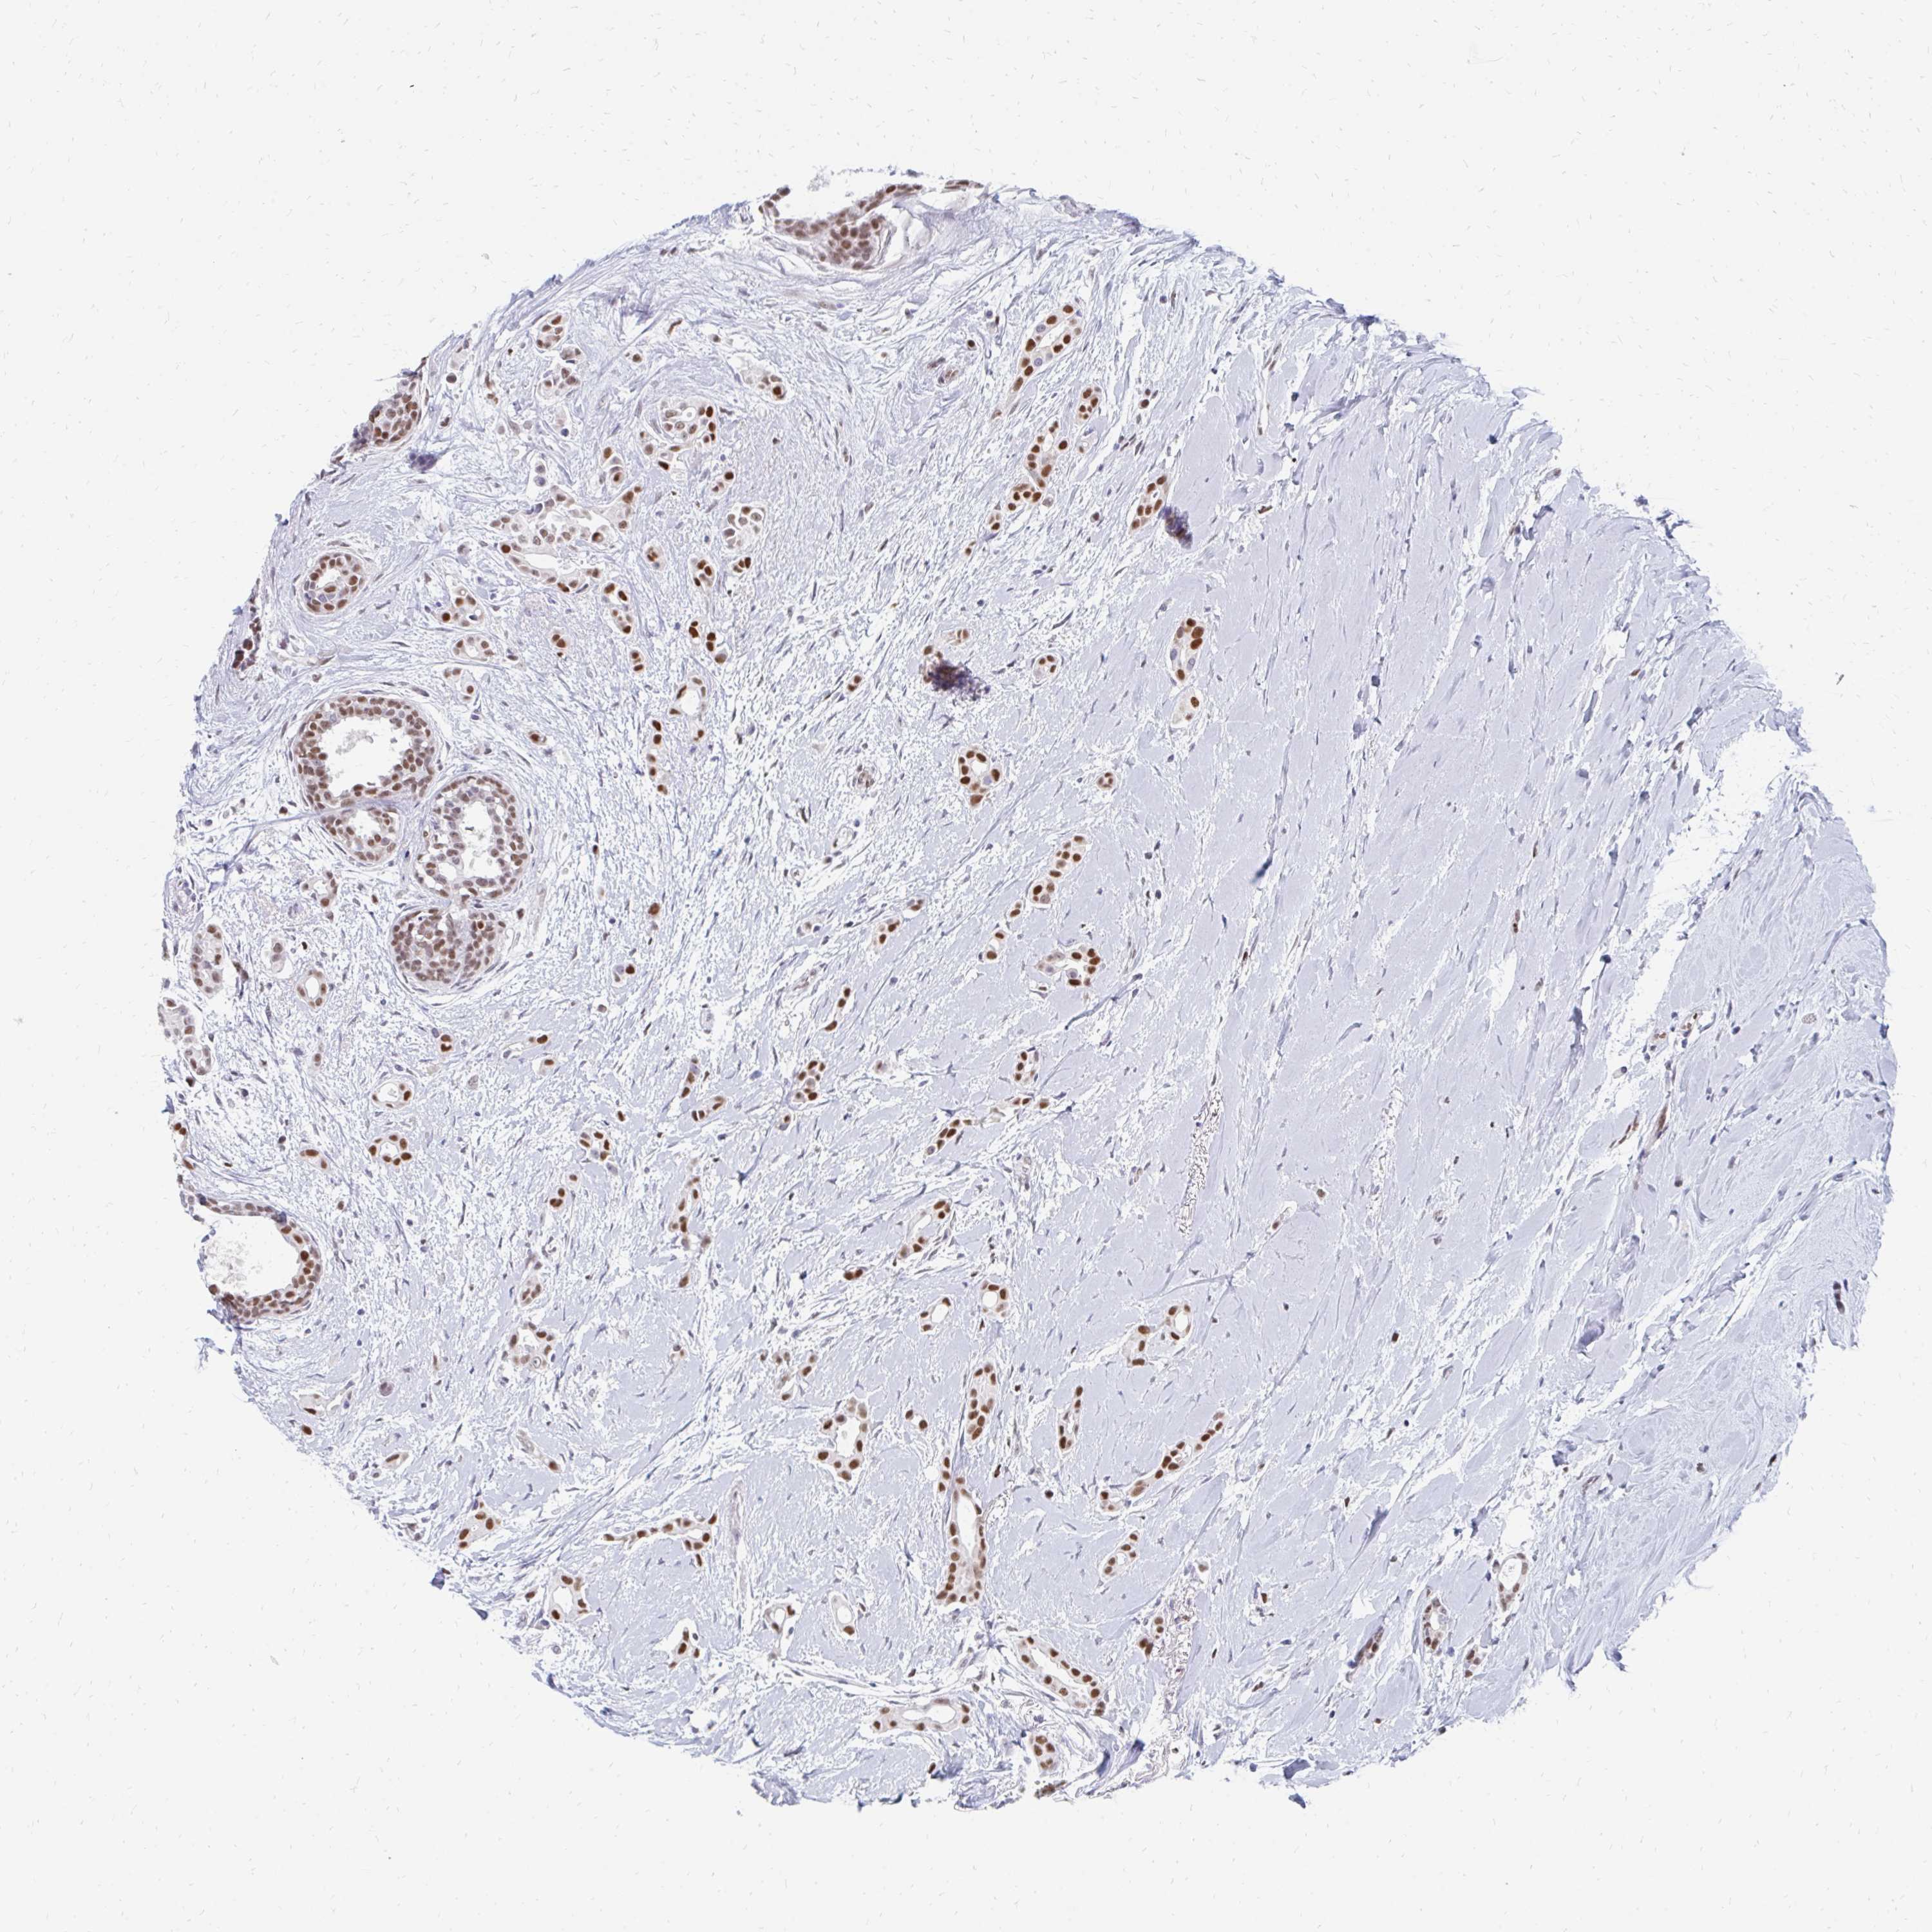

BRCA TCGA BRCA VALIDATION PROTEIN EXPRESSION